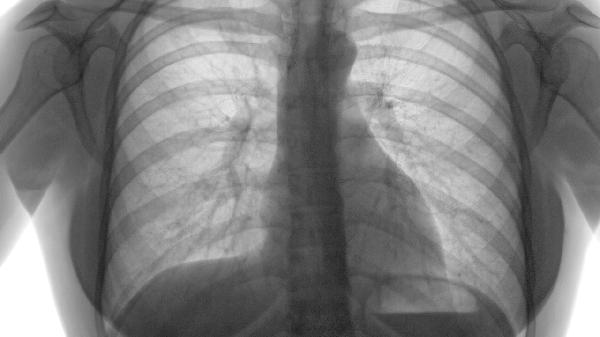

对于血氧饱和度低于88%的患者,长期家庭氧疗可改善缺氧状态,每日吸氧时间需超过15小时。便携式制氧机便于活动时使用,夜间氧疗能预防肺动脉高压。氧疗期间需监测血气分析,避免二氧化碳潴留。

严重肺大疱患者可考虑肺减容术切除病变组织,终末期患者需评估肺移植指征。手术风险较高,需全面评估心肺功能。术后需加强呼吸道管理,预防感染和并发症。部分患者可采用支气管镜介入治疗。